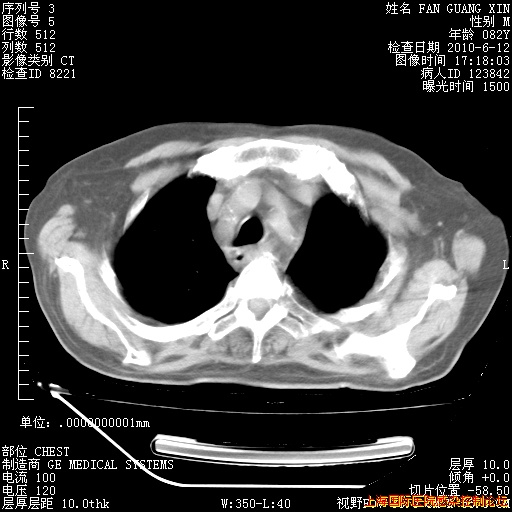

补发6月12日肺部CT肺窗

6月12日肺窗

整整相隔30天的肺部CT好像有所好转啊。甲强龙减量第3天,需要观察体温。